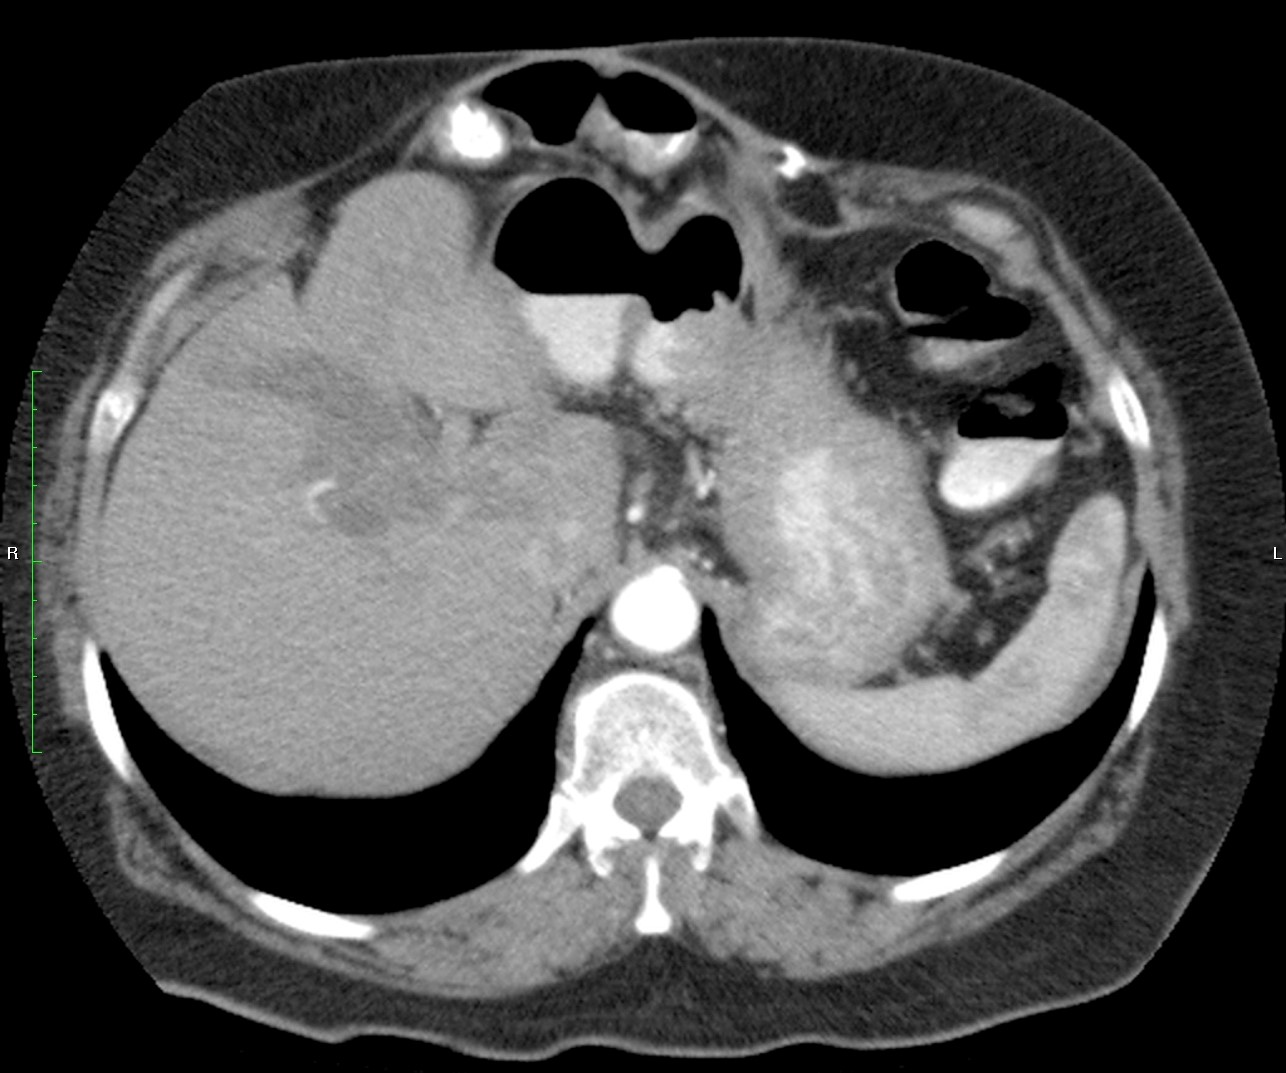

Mujer de 57 años.

Cuadro clínico de 1 mes de evolución caracterizado por distensión abdominal e hiporexia.